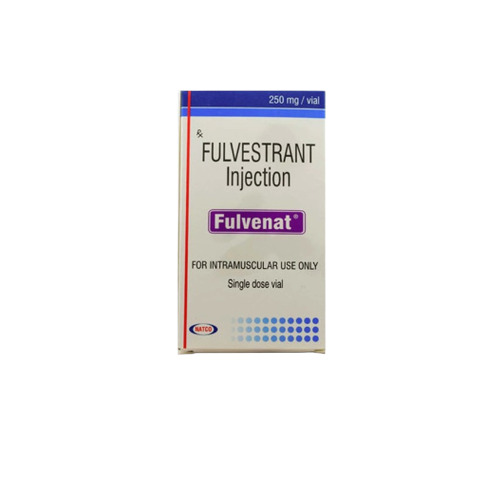

Trending products